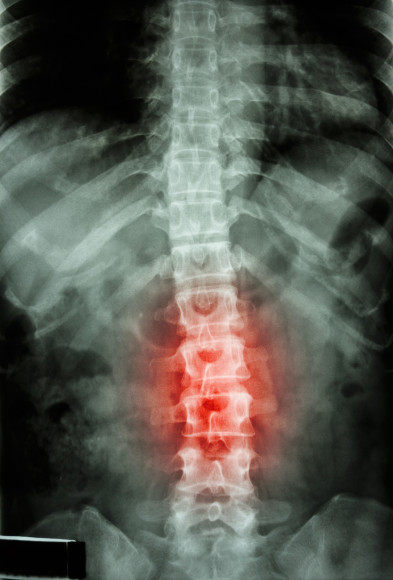

According to a Workers Compensation Research Institute (WCRI) study, “Why Surgery Rates Vary,” back pain is a critical issue in workers’ compensation. Approximately one-fifth of the injuries covered by workers’ compensation are back injuries.

Although back pain is common, how to best treat the injury, including if and when surgery is clinically appropriate, is controversial and lacks clinical consensus. Moreover, the frequency of surgery among workers with back injuries varies widely from state to state, according to WCRI. For example, nearly 20 percent of injured workers with back pain had surgery in Oklahoma and Tennessee. By contrast, less than 10 percent of workers in California and Florida with the same diagnoses had surgery.